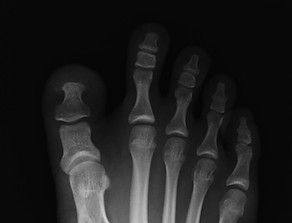

外反母趾(がいはんぼし)

外反母趾とは、親指が人差し指側に「く」の字状に曲がった状態の事をいいます。

原因は様々で必ずしもヒールをはいたから発症する病気ではありません。

遺伝的影響として、足の形や足趾間の靭帯・筋肉の緩みや弱さなどによる軟部組織のアンバランスなども考えられます。